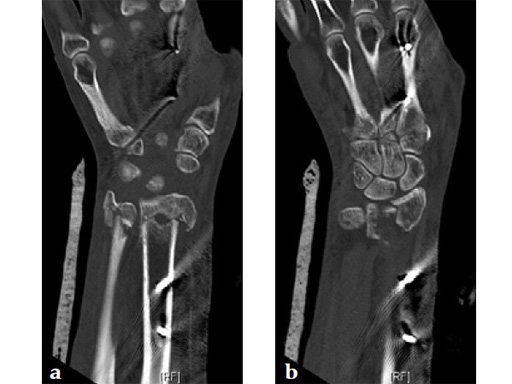

Fig 2a-b Comparison of anatomical bend and screw placement of volar rim DR plate (a) and DR juxta-articular plate (b).